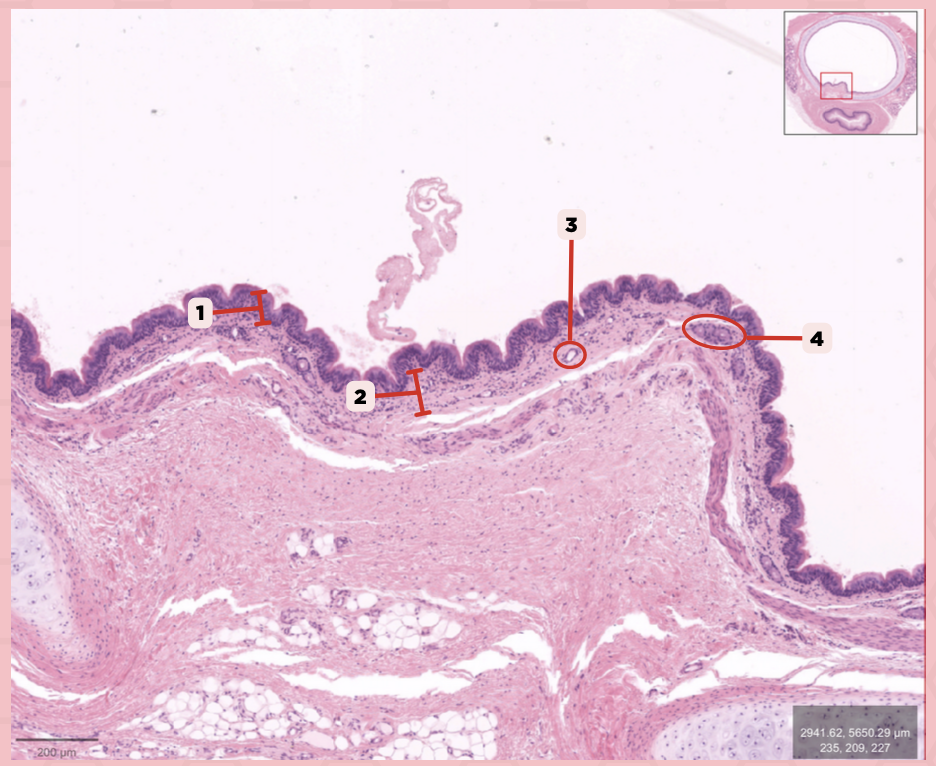

Identify the structure labeled as 1.

Nasal septum

Identify the structure labeled as 2.

Nasal cavity

Identify the structure labeled as 3.

Hard palate

Identify the structure labeled as 4.

Mucosal Associated Lymphoid Tissue (MALT)